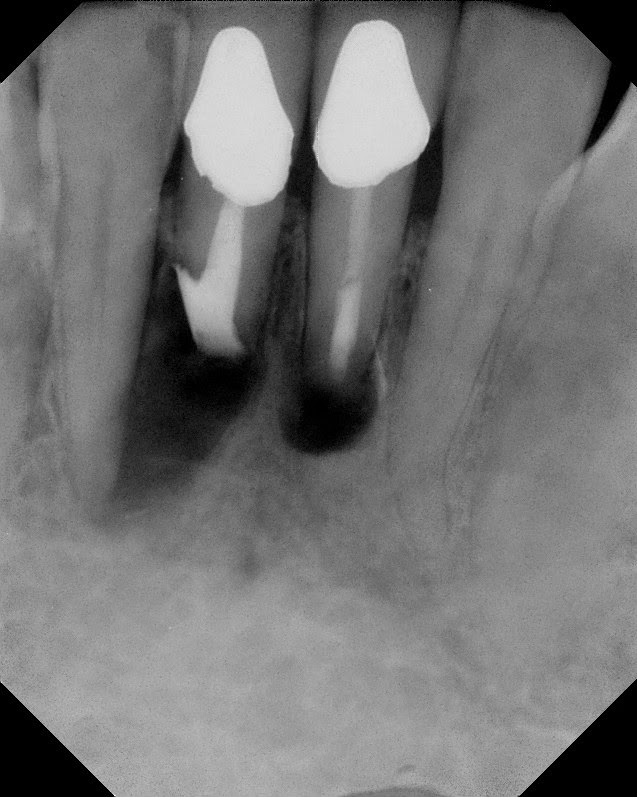

1 Year Recall

2 Year Recall - complete bony healing.

We should not forget how lucky we are to work in a biologic enviroment that is so forgiving and with such ability to regenerate bone.